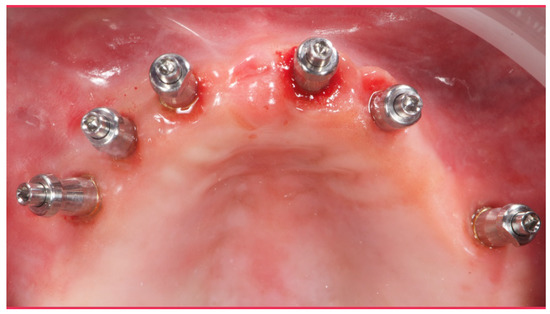

Figure 5.

Intraoral picture of the implant positions and the multi-unit abutment screwed on.

Before definitive impression, multi-unit abutments were unscrewed, the implant connections were cleaned, and six OT Equator Titanium Abutments (Rhein’83, Bologna, Italy) with TiN coating were screwed (Figure 6), according to the manufacturer. Immediately after, the patient received a digital impression (CS 3600 intraoral scanner, Carestream Dental, Milan, Italy), taken at abutment level (Figure 7), using dedicated scan abutments (OT Equator Titanium Scan Abutment, Rhein’83). However, overlapping of the captured images failed to produce an accurate impression, maybe due to the disparallelism of the implant ranging from 65° to 86°. Hence, a prototype model was created and a convention gypsum impression [16] with a customized impression tray was taken at abutment level using conventional impression coping (Titanium Impression Coping, Rhein’83; Figure 8 and Figure 9). Esthetics, phonetics, the occlusal vertical dimension, and the centric relation were verified and approved by both the clinician and the patient (Figure 10 and Figure 11). Only after that, a definitive cast, implant position, and esthetic try-in were digitalized and a CAD/CAM titanium bar (NewAncorvis, Bologna, Italy) was anatomically designed with a dedicated software (Exocad DentalCAD, Exocad, Darmstadt, Germany) by a certified dental technician (MA), according to the prosthetic contours and the implant position. Three projects were created with a three-, two-, or one-piece CAD/CAM titanium bar, respectively (Figure 11b). Each of these projects failed to create an accurate titanium bar able to respect the minimum restorative space required by the prosthetic volume of the tried prosthesis, due to the multiple components involved (attachment system, prosthetic framework, artificial acrylic composite teeth, and pink acrylic base). Hence, a fourth project was created with a CAD/CAM titanium bar designed for a fixed screw-retained restoration, initially excluded due to the implant disparallelism. In order to overcome the undercuts created by the tilted implants, and to produce a passive-fit CAD/CAM titanium bar, abutments with an extragrade system were applied (Figure 11c). Extragrade is a special titanium abutment which has the possibility of entering, even in cases of strong disparallelisms, thanks to its internal design. On a large number of implants (those positioned worse from the point of view of the emergence profile), we cannot put the through screw. In this case, the abutment will be retained by the white Seeger only. The number of abutments without screws was limited to two, according to the manufacturer and considering the overall number of placed implants. Moreover, an angulated screw channel concept was applied to avoid the access hole in the vestibular area of the anterior teeth, moving the access holes in the pink area of the hybrid prosthesis. The fit of the implant bar was clinically and radiographically tested in the patient’s mouth, according to established criteria ([17,18,19]; Figure 12). It was important to position the flat surfaces of the abutment-bar connections in correspondence with the undercut created by the inclination of the implant; the flat surface indicates the location of the extragrade bevel, which allows the framework to overcome the undercuts created by the tilted implants. After that, an interocclusal record was taken in centric relation, and the prosthesis was delivered. The screw-retained fixed complete implant-supported prosthesis was seated in the patient’s mouth using the snap-on function offered served by the Seeger System (Figure 13). Four out of six screws were tightened according to the manufacturer, and the screw-holes were closed using composite pink materials. Finally, the occlusion was adjusted and radiographs were taken. The patient was scheduled for hygiene maintenance and control every 4 months (Figure 14, Figure 15 and Figure 16).